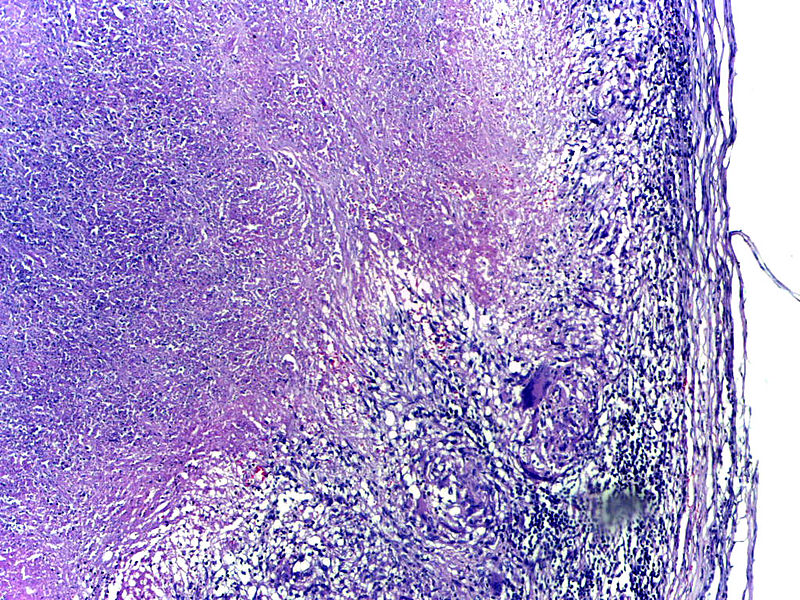

Histology of tuberculosis (TB) shows caseating granulomas, and positive acid-fast bacilli (AFB) stain.

Tuberculosis (TB) results in the hilar lymph nodes undergoing fibrosis and calcification to produce a Ghon complex as well as localized, caseating necrosis of the lung.

Tuberculosis (TB) usually occurs at the lung’s apex due to the high oxygen tension in that region of the lungs.

Tuberculosis (TB) creates a cavitary foci of caseous necrosis and has the potential to cause tuberculous bronchopneumonia or miliary pulmonary tuberculosis.